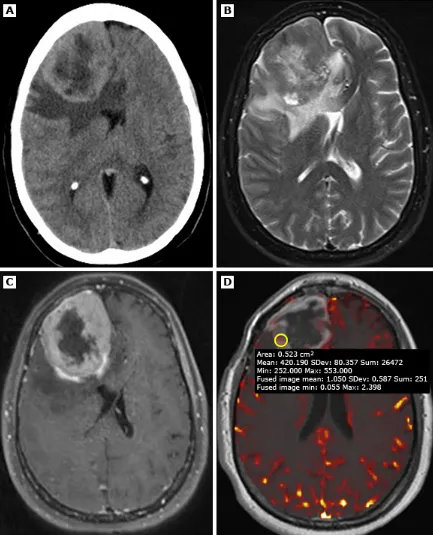

案例八:49岁患者,病理证实为WHO 3级(间变性)脑膜瘤。A(平扫CT):右额叶巨大占位,密度不均,周围血管源性水肿,明显占位效应。B(T2加权MRI):肿块信号不均,周边见相对于高信号核心的厚壁低信号环。C(增强MRI):强化肿块内部见中央强化减低区,提示坏死。D(灌注加权MRI):相对脑血容量(rCBV)未见升高。

但上述表现敏感性和特异性均有限。多数脑膜瘤首选手术治疗,具体方案取决于病灶大小、部位、患者全身状况和症状。部分研究发现高级别脑膜瘤在18F-FDG-PET中摄取更高,但诊断价值有限。新型PET示踪剂(如Ga-68 DOTATATE)为诊断和治疗规划带来新希望,尚未临床普及。